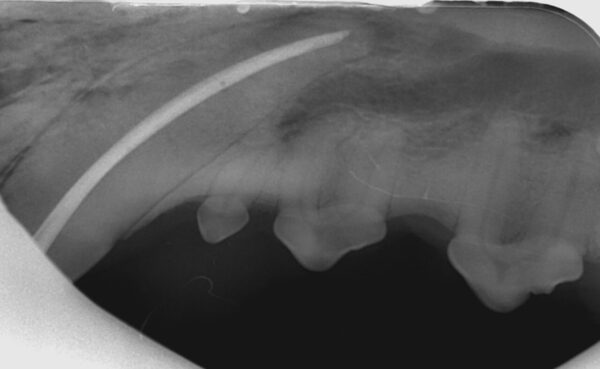

- En el gato, el foramen mentoniano se encuentra en el espacio interdental entre el diente canino y el tercer premolar mandibular o a nivel de este último (imagen 5).